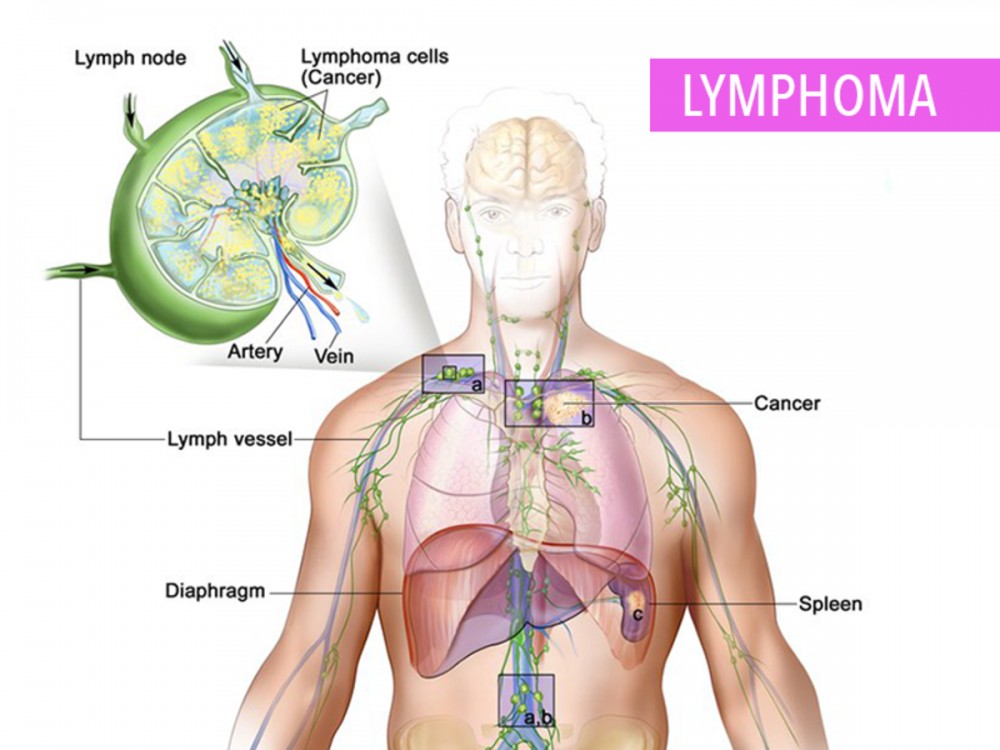

Изображения и схемы: как выглядит лимфа